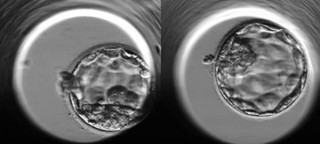

78η ώρα: Τα κύτταρα «κολλούν» το ένα με το άλλο και φαίνεται να συνενώνονται. Ένα έμβρυο που «συμπυκνώνεται» πριν την 90η ώρα έχει πολύ καλές πιθανότητες για την εξέλιξή του.

114η ώρα: Δύο βιώσιμα έμβρυα: ένα «τέλειο» κι ένα «πολύ καλό».